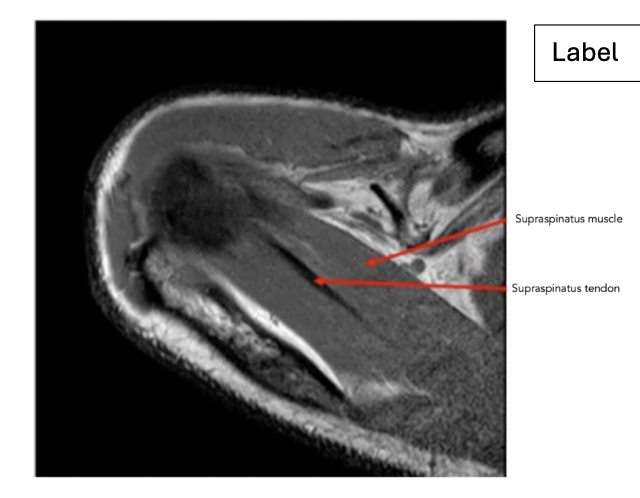

What is the most common rotator cuff tendon tear?

• Supraspinatus tendon

What is the sequence and why?

• T1 – fluid is dark but fat is bright

Sequence + pathology?

• PD, PDFS

• Path = supraspinatus tendon tear

• -  You can follow the tendon and see that it stops just above the humeral head rather than

attaching to the lateral aspect of the head.

• -  More prominent of the PDFS you can see high signal around the lateral aspect of the humerus

indicative of a pathological process occurring because of the tear.